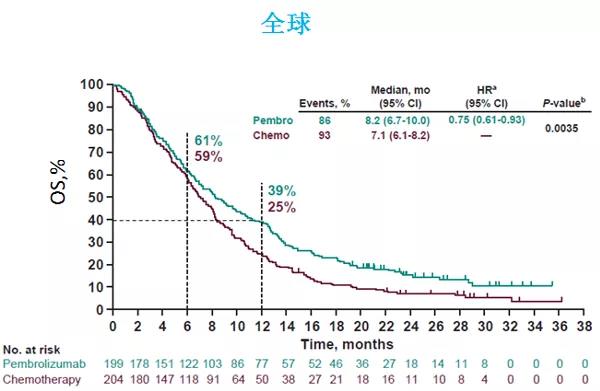

2020年的金秋,欧洲肿瘤内科学会(ESMO)年会如期而至,免疫治疗在消化系统肿瘤的治疗中大放异彩。其中食管癌领域最重磅级研究——Keynote-590研究在...